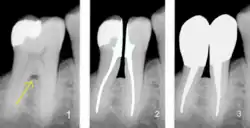

Eine günstige Wurzelform weisen Zähne mit gespreizten Wurzeln auf, wie sie in der Abbildung an den Molaren zu sehen sind. Ebenso erhöht sich die Pfeilerwertigkeit durch die Form der einzelnen Wurzel, die im günstigen Fall eine zylindrische Form aufweist (in der Abbildung der zweite Zahn von links – Eckzahn 23). Ungünstig sind konisch zulaufende und kurze Wurzeln.

Furkationsgrad

Als Bifurkation (bei zweiwurzligen Zähnen) oder Trifurkation (bei dreiwurzligen Zähnen) wird die Aufteilungsstelle der Zahnwurzeln bei mehrwurzeligen Zähnen bezeichnet. Beim parodontal gesunden Zahn liegen sie innerhalb des Kieferknochens und sind weder sicht- noch sondierbar. Bifurkation und Trifurkation werden in vier Furkationsgrade eingeteilt. Eine freiliegende Furkation, die durch parodontalen Knochenabbau entstanden ist, bildet einen potentiellen Entzündungsbereich, der oftmals schwer zu reinigen ist. Je nach Ausprägung kann eine freiliegende Furkation die Pfeilerwertigkeit reduzieren.[12]

1) Freiliegende Bifurkation (Pfeil);

2) Prämolarisierung und Wurzelkanalbehandlung; 3) Zustand nach Überkronungen mit Stiftaufbauten;

(Darstellung durch Bildbearbeitung);